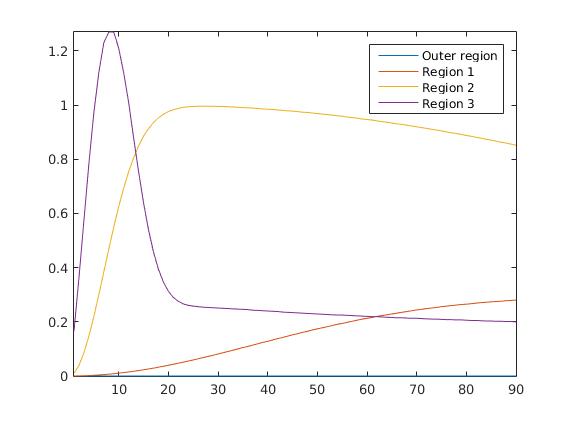

To test our reconstruction method, we created different synthesized data sets consisting of pixels with varying complexity of the image structure and with a different number of subregions and a total of 90 time steps in each sequence. Based on these subregions, we created three-dimensional matrices containing the true image in one time step within each slice. The underlying concentration in each subregion is related to a realistic shape of a the time-dependent behaviour of the tracer in different tissue types.

The first data set consists of a heart-shaped region and three circles on a static background (see figure 1 (a)). The two smaller circles are assumed to belong to

the same tissue type and therefore to the same subregion, which causes a total of four subregions, including the background. To simulate a more realistic application of dynamic SPECT

imaging, we used a synthesized representation of a rat liver as a second data set (see figure 1 (b)). The temporal concentration curves used to simulate the data sets

are shown in figure 2. As before, the total number of subregions was chosen to be equal to four in order to provide a both simple and realistic shape model.